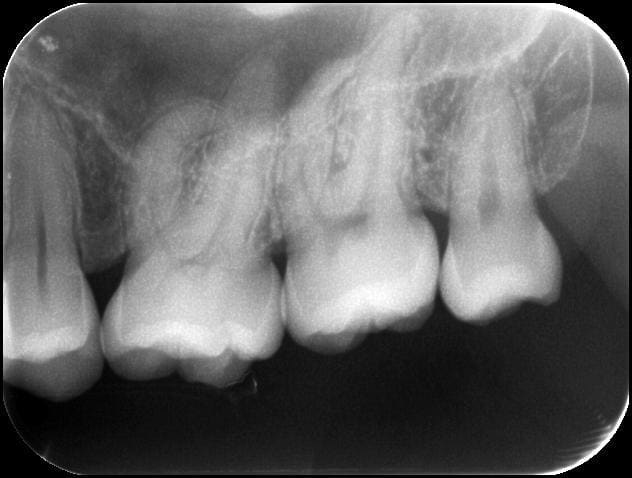

Transplantation de 18

sur une agénésie de 35

cf la 28 tjrs en place

Transplantation de dds 35 18 xxievm - Eugenol

Transplantation de dds 28 w8tbre - Eugenol